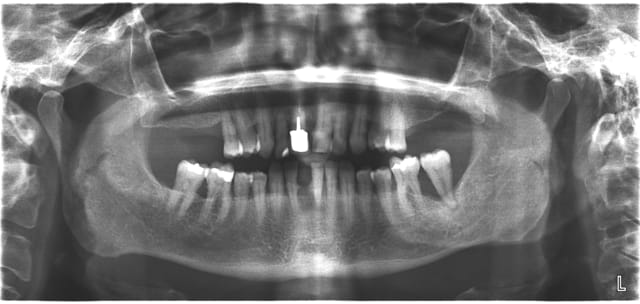

j'ai une patiente de 60 ans qui a consulté ce matin pour "mettre une dent" au niveau de 41. 31 est légèrement mobile, 32 et 42 ne sont pas mobiles. L'hygiène est très moyenne et la demande esthétique et le budget peu élevés. J'envisage de faire une contention paro avec une dent facette au niveau de 41 afin de temporiser et quand le moment sera venu, de faire un stellite. Qu'en pensez-vous? Quels matériaux utiliseriez-vous?

Mets des molaires en haut et vite! Parce qu'avec une paro comme ça sinon t'es bon pour extraire les deux blocs antérieurs très rapidement (en plus de traiter la paro et enseigner l'hygiène).